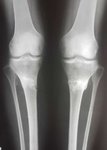

Дата операции 15.03.2017г.

Дата снятия аппаратов 23.06.2017г.

Срок лечения 97 дней.